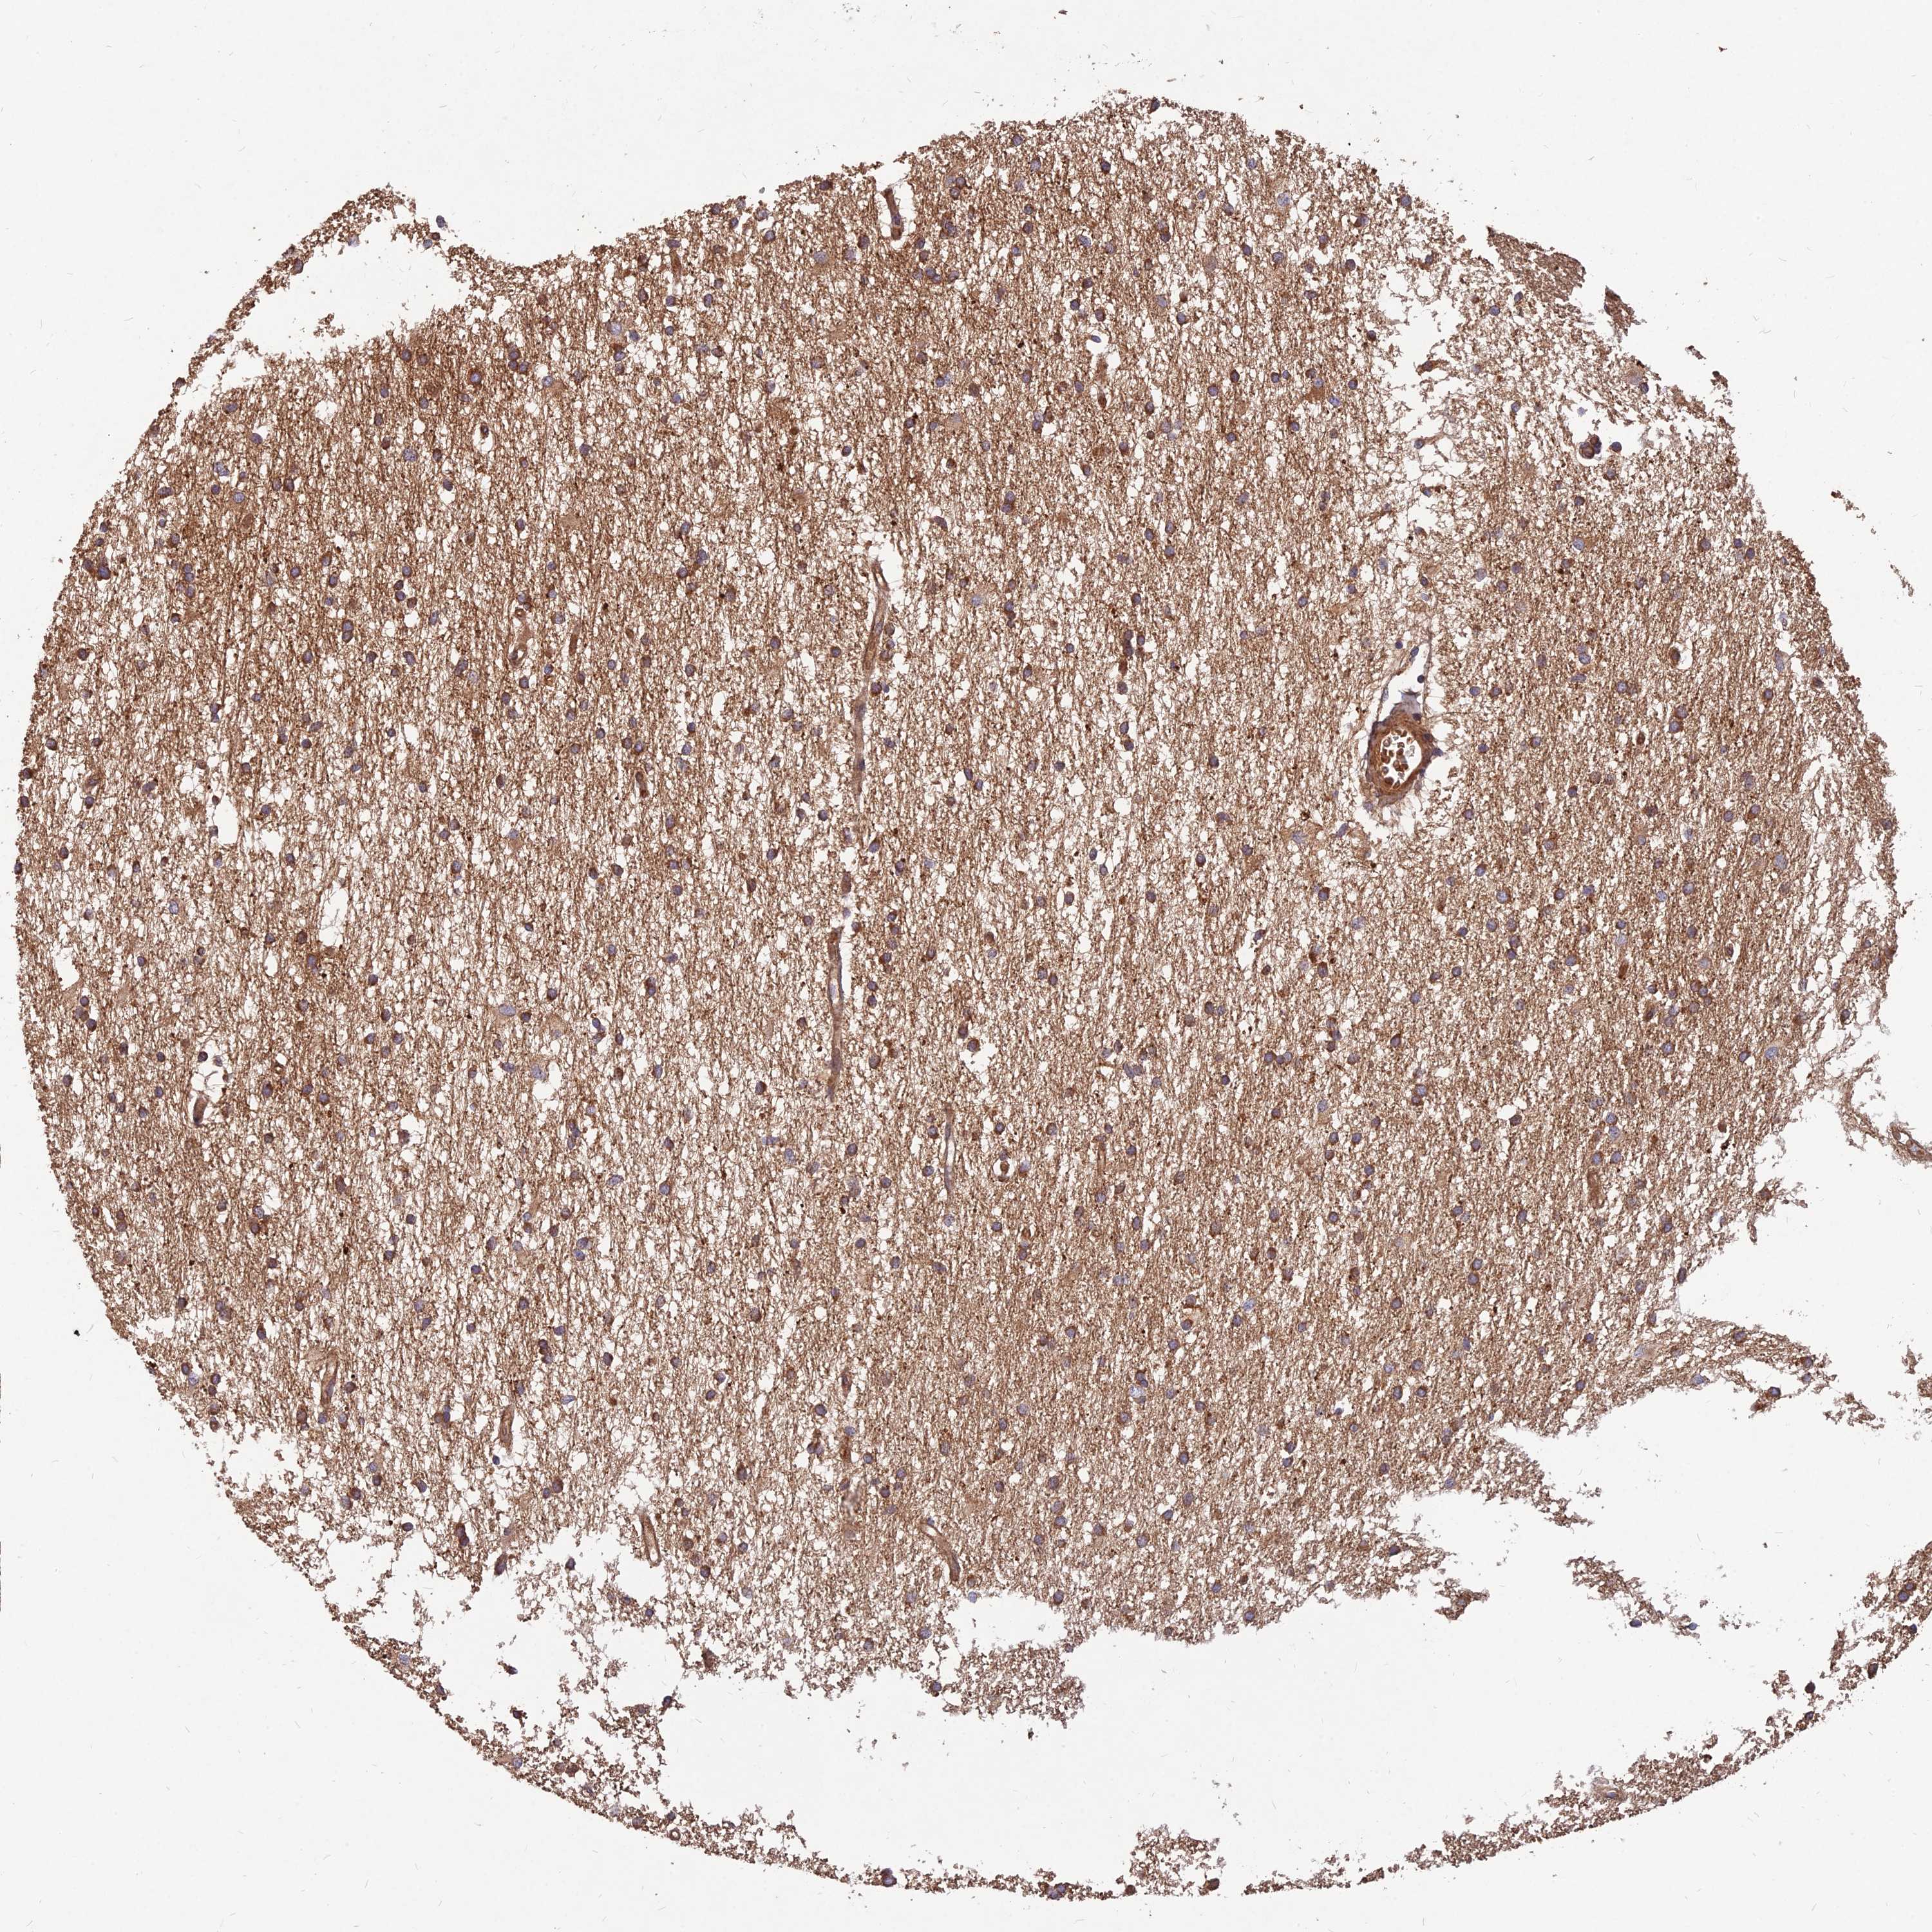

GLIOMA - Protein expressioni

A mouse-over function shows sample information and annotation data. Click on an image to view it in a full screen mode. Samples can be filtered based on level of antibody staining by selecting one or several of the following categories: high, medium, low and not detected. The assay and annotation is described here.

Note that samples used for immunohistochemistry by the Human Protein Atlas do not correspond to samples in the TCGA dataset.

Antibody stainingi

Antibody staining in the annotated cell types in the current human tissue is reported as not detected, low, medium, or high, based on conventional immunohistochemistry profiling in selected tissues. This score is based on the combination of the staining intensity and fraction of stained cells.

Each image is clickable and will lead to virtual microscopy that enables deeper exploration of all samples and also displays staining intensity scores, fraction scores and subcellular localization as well as patient and tissue information for each sample.

Antibody HPA039708

Antibody HPA040038

Staining

High

Medium

Low

Not detected

Intensity

Strong

Moderate

Weak

Negative

Quantity

>75%

75%-25%

<25%

None

Location

Nuclear

Cytoplasmic/membranous

Cytoplasmic/membranous,nuclear

Glioma, malignant, High grade

Glioma, malignant, Low grade